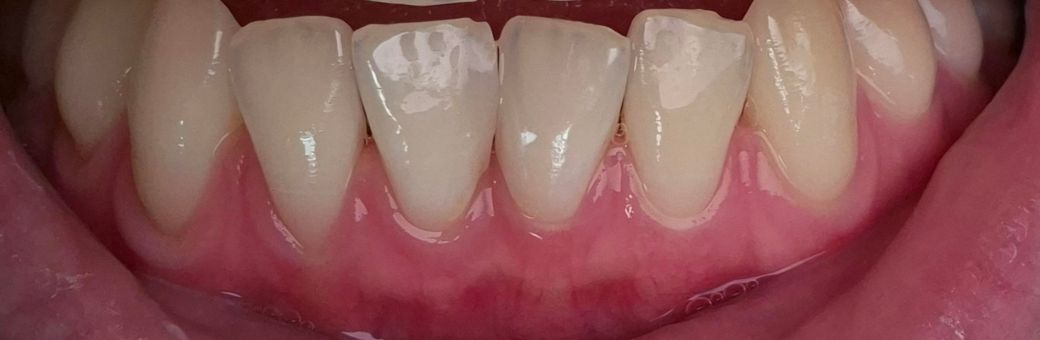

25살 잇몸뼈 상태 심각한가요???

아래앞니 쪽이 아파서 두 치과에 갔는데

첫번째 치과에서는 잇몸뼈만 조금 내려갔다고 하고 염증이나 충치도 아예 없고 아래앞니쪽 치석이 있는 편이니 스케일링만 받으면 된다고 했어요.

두번째 치과에서도 아래앞니에 문제는 없고 아레앞니 잇몸이 약한 편이니 양치질만 살살 하라고 하더라고요.

*참고로 아래앞니는 미관상 안 좋아서 중절치 2개를 레진으로 떼운 적이 있습니다 약 8년 정도 되었는데 레진 상태도 양호하다고 합니다.

• 1번 째 사진